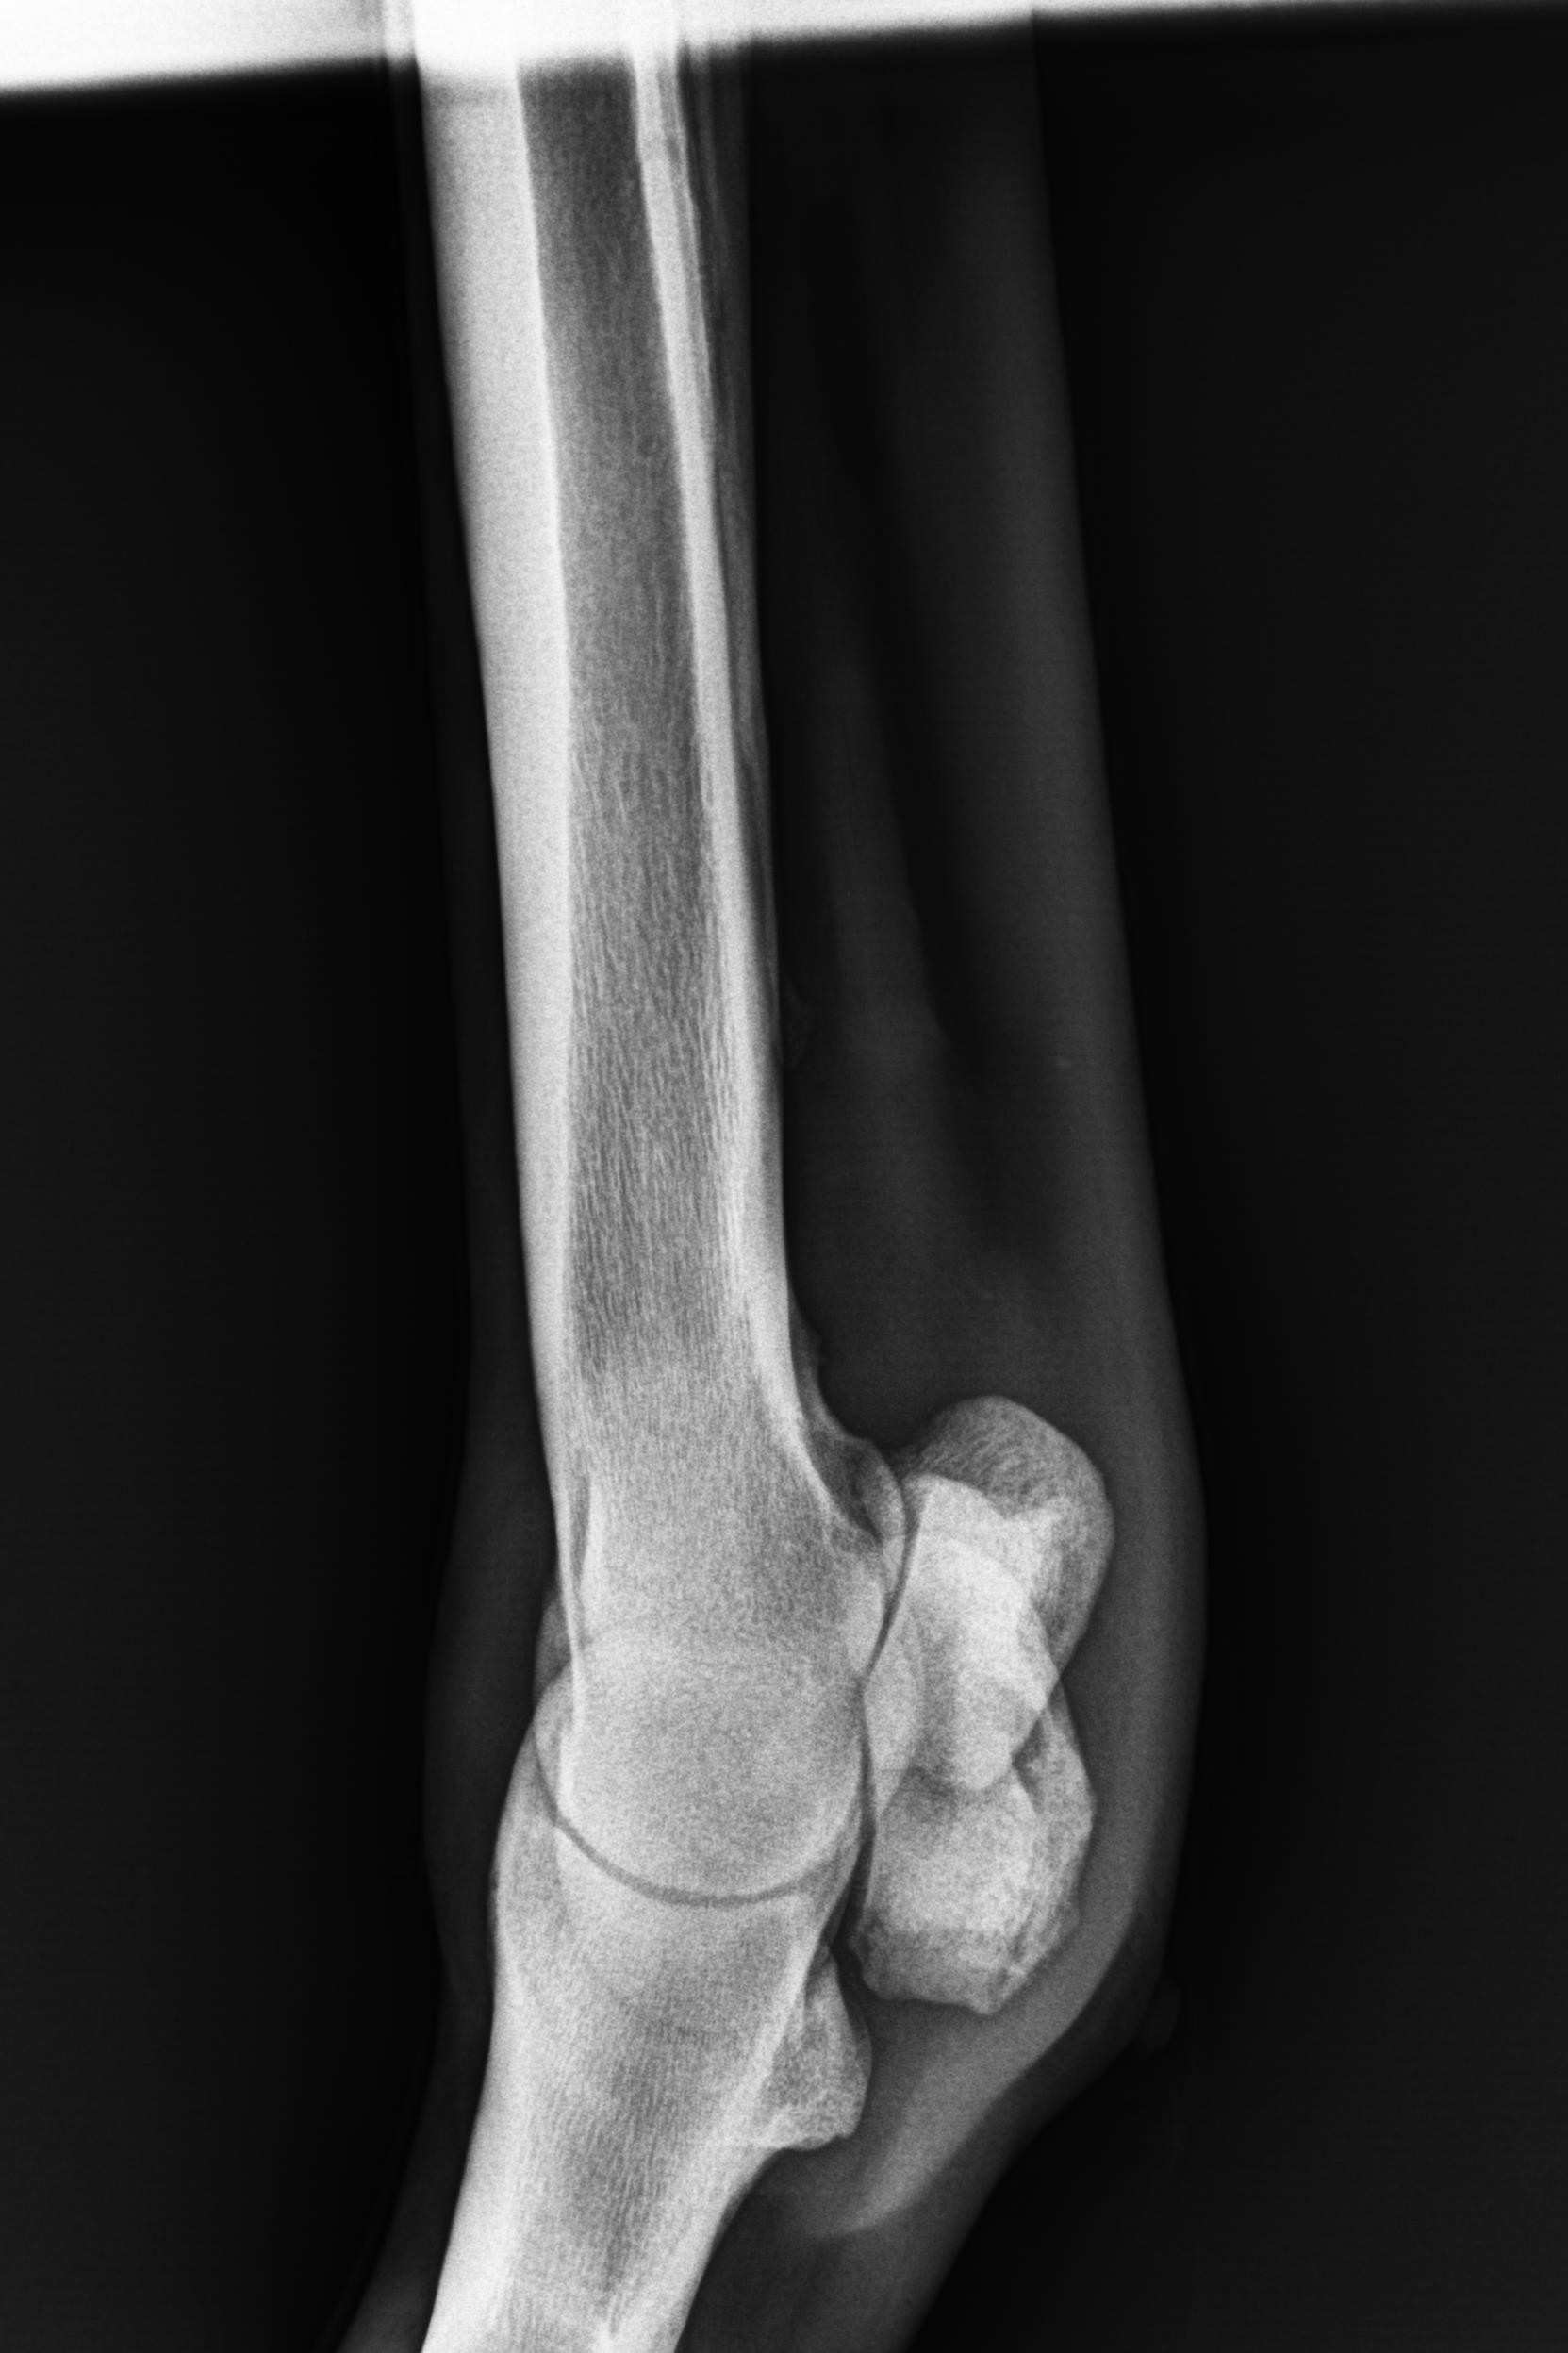

そんな状況の中、1月9日にレントゲン検査を受けると「左前肢外側の種子骨のボーンシスト」が原因と判明しましたので、サラブレッドオークションへ出品とさせていただきます。現状のままでは競走馬としてのデビューは難しいかも知れません。皆様には現状をご理解いただき、事前に獣医検査を受ける等、ご納得をいただいた上でのご検討、ご入札をお願いし、現状渡しのノークレーム、ノーリターンでお願いいたします。

セールの後からお預かりして来ましたが、レントゲン検査を受けて獣医から「このまま調教を進めたら骨折するリスクが大きい」との所見でした。競走馬は勿論ですが、現状のままでは乗馬としても厳しいと思います。(Team百馬力・原翼氏)